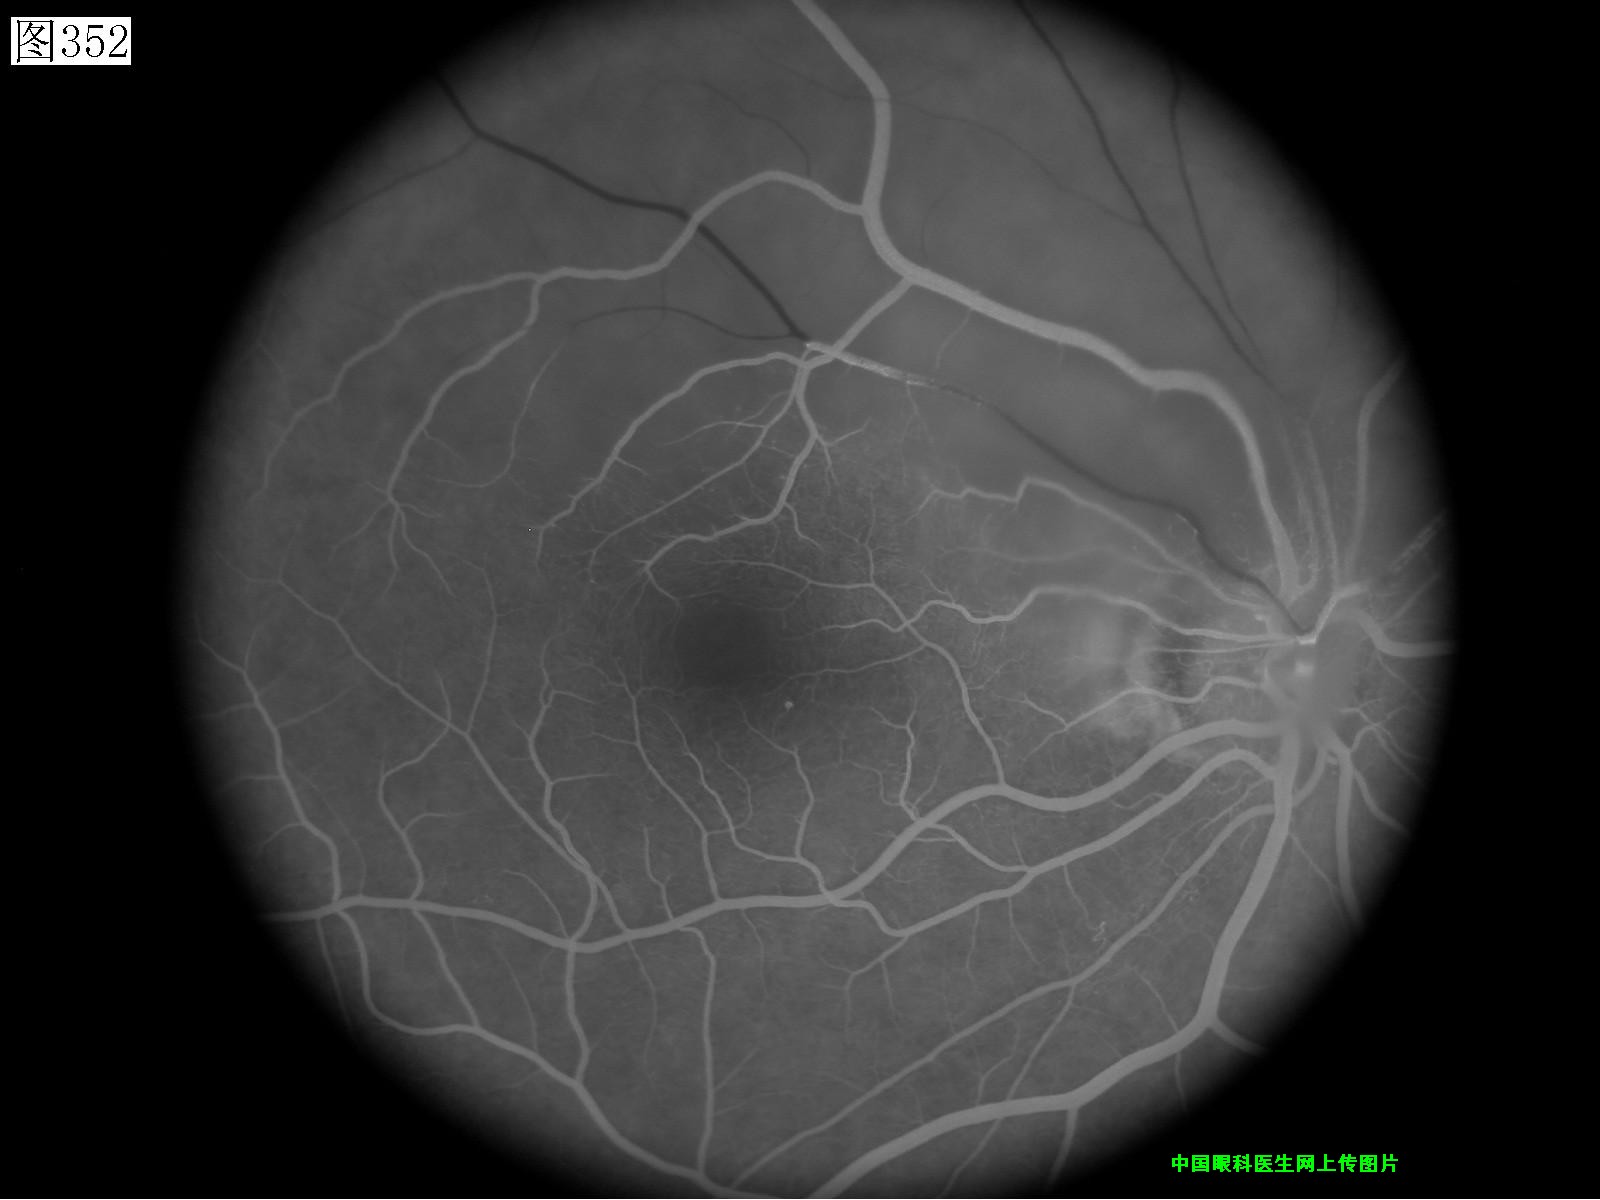

349 350 351 352